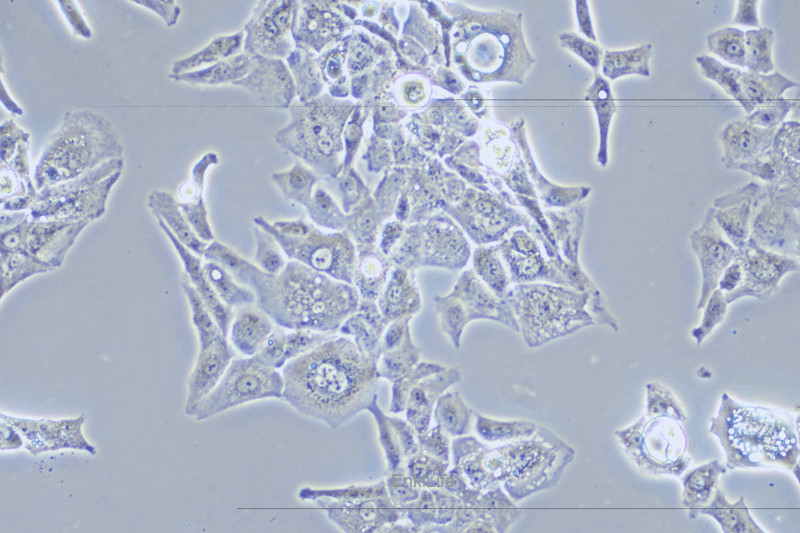

MUG-Chor1是一种间充质样细胞系,于2009年从一名57岁白人女性脊索瘤患者的骶骨中分离出来。脊索瘤是一种罕见的生长缓慢的肿瘤类型,MUG-Chor1是一种生长相对缓慢的细胞系。MUG-Chor1具有异质形态,由浆液细胞和粘液性细胞间质组成,代表典型的脊索瘤特征。这些细胞含有转录因子T(Brachyury)的扩增(脊索瘤最特异的标记)以及PTEN的缺失。

细胞形态

间充质样(长梭形不规则形状)